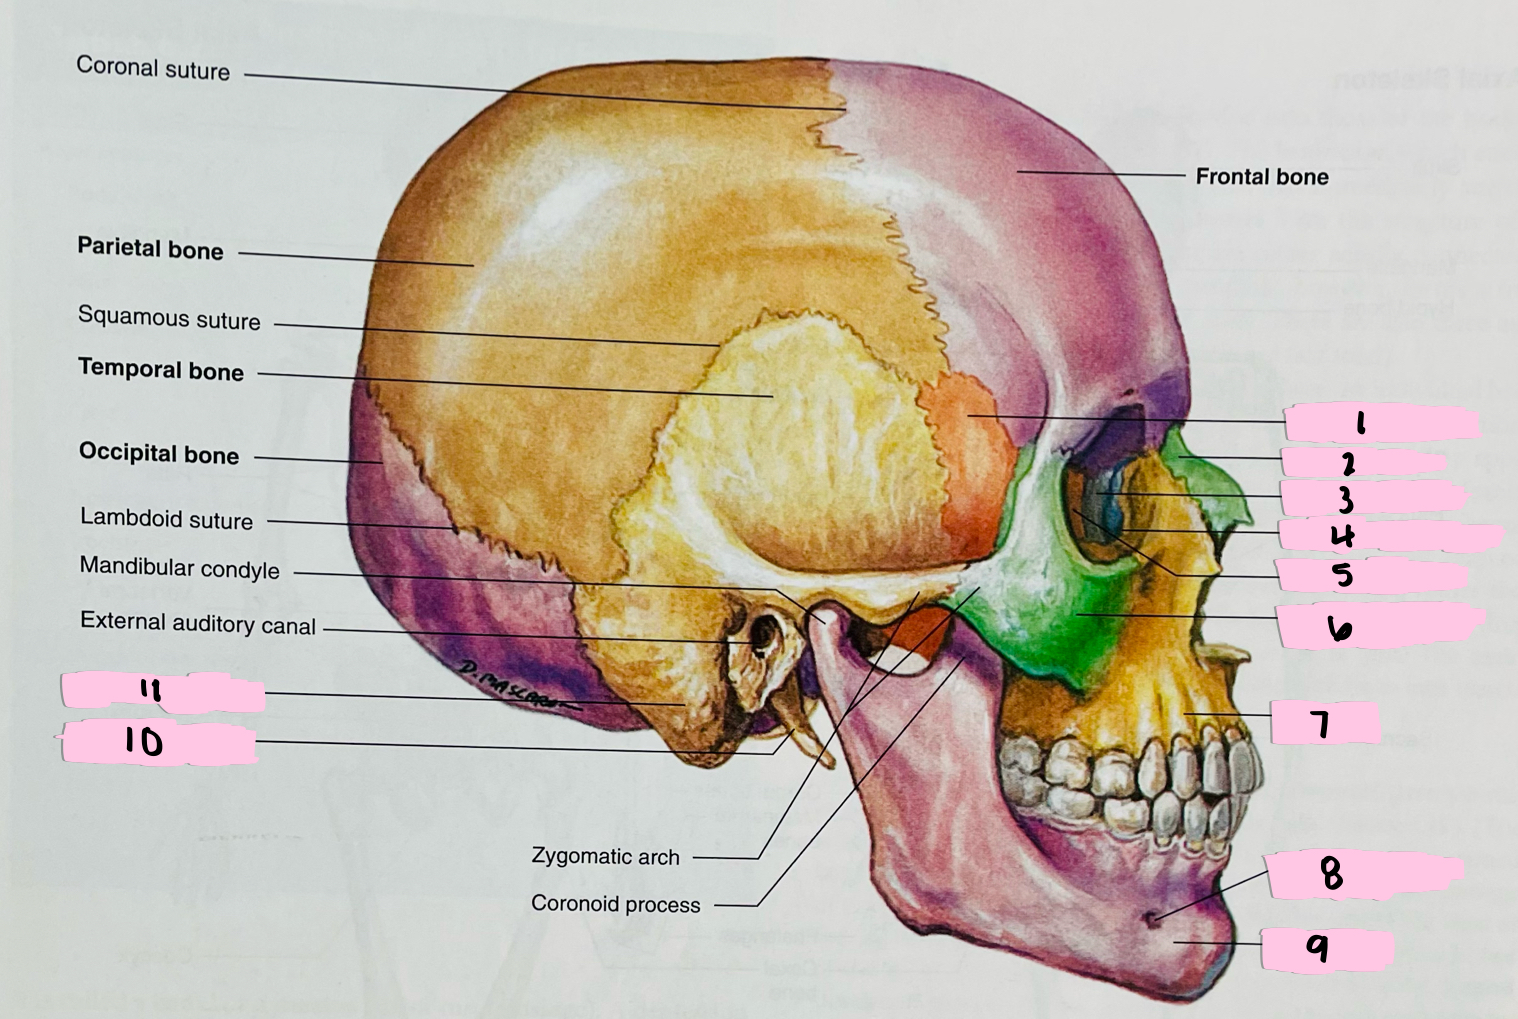

What is 1 pointing to?

Sphenoid bone

What is 2 pointing to?

Nasal bone

What is 3 pointing to?

Lacrimal bone

What is 4 pointing to?

Nasolacrimal canal

What is 5 pointing to?

Ethmoid bone

What is 6 pointing to?

Zygomatic bone

What is 7 pointing to?

Maxilla

What is 8 pointing to?

Mental foramen

What is 9 pointing to?

Mandible

What is 10 pointing to?

Styloid process

What is 11 pointing to?

Mastoid process